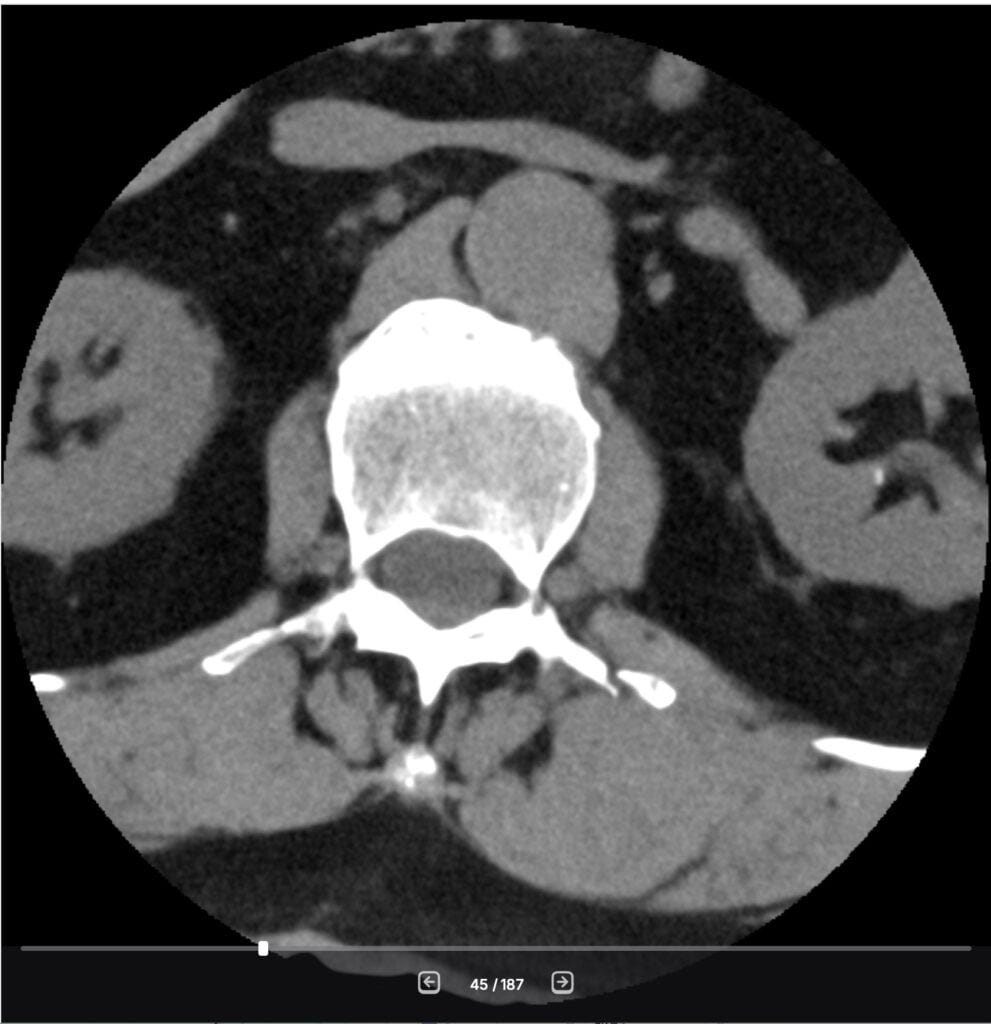

Because this is what you need to do when you have ‘minor fractures‘ of the transverse processes on your spine, as can be seen in my CT scan after my incident in November.